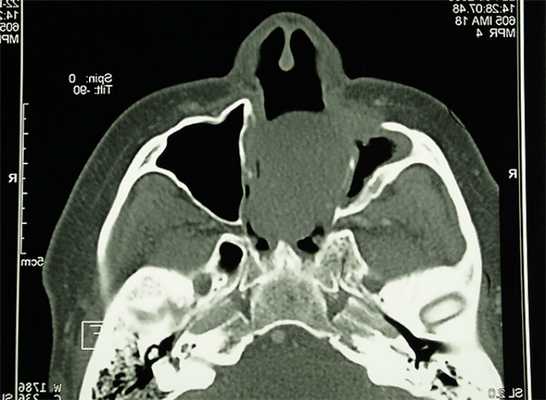

На кафедру ортопедической стоматологии из онкологического диспансера Екатеринбурга была направлена на консультацию пациентка Г., 64 лет, по поводу рецидива хондромы верхней челюсти (рис. 1).

Рис. 1. Хондрома верхней челюсти.

Анамнез: 4 года назад была проведена первая операция по поводу хондромы верхней челюсти, месяц назад был поставлен диагноз: рецидив хондромы верхней челюсти. В полости рта в передней трети твердого неба отмечается безболезненный узел с неровной поверхностью размером 8х15 мм и сквозной дефект, сообщающийся с гайморовой пазухой размером 7х10 мм (рис. 2).